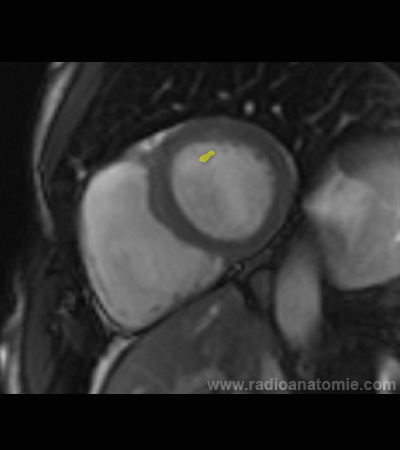

Radioanatomie et plans de coupe en IRM cardiaque

Pilier de la valve mitrale

Ventricule gauche

Ventricule droit

Septum interventriculaire